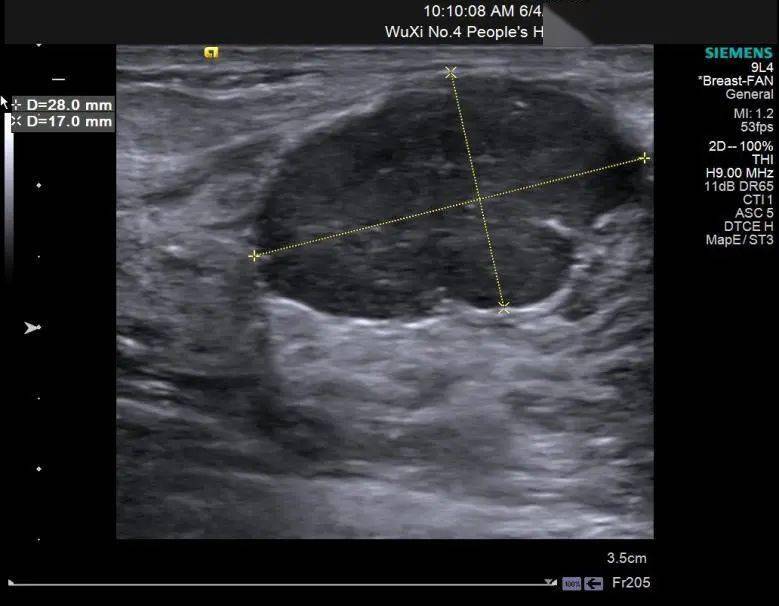

乳腺纤维瘤?

图片尺寸720x576